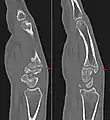

Additional images